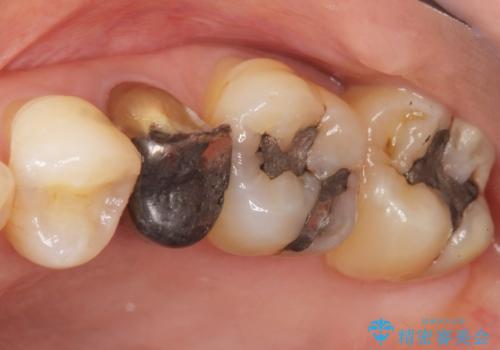

- 歯が欠けてしまったことを主訴に来院された患者様です。

欠けている奥歯(左上5)は失活歯で、保険内の銀の詰め物(メタルアンレー)で治療されていました。

金属の詰め物と土台を除去し、ファイバーコア(金属を使わない強くてしなやかな土台)を植立したのちセラミッククラウンによる補綴治療を行いました。

精査したところ、右上の奥歯(右上5)に根尖病変を認めたため、こちらは根管治療後にセラミッククラウンによる補綴を行いました。